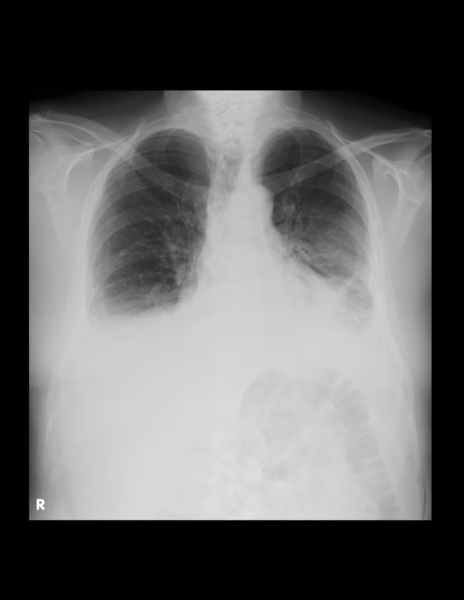

-Campos pulmonares, ambos con presencia de atelectasias basales

-Recesos costofrénicos y cardiofrénicos ocupados.

OPINIÓN RADIOLÓGICA:

EN EL PRESENTE ESTUDIO RADIOGRÁFICO, EXISTEN ATELECTASIAS BIBASÁLESES CON DERRAMÉ PLEURAL ASOCIADO.

CARDIOMEGALIA GRADO II.

CAMBIOS OSTEODEGENERATIVOS Y ATEROESCLEROSIS.